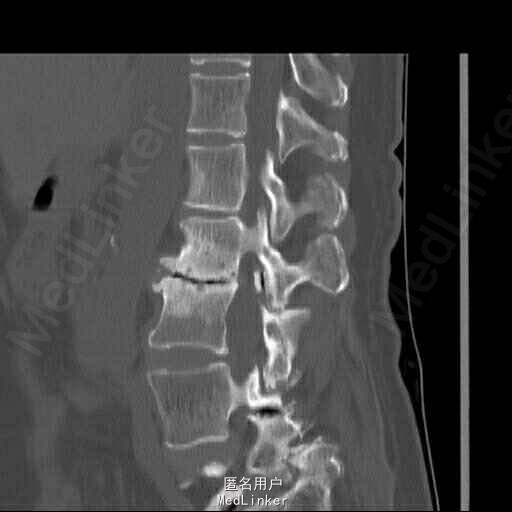

查体:脊柱侧弯,上肢无麻木,疼痛感觉异常,腰部右侧疼痛,右下肢及右臀部疼痛,麻木感。双侧肌力及肌张力可,膝腱反射(+),踝反射(+),病理征(—),直腿抬高试验。右侧40度,左侧55度。 辅助检查:腰椎x线片:腰椎侧弯,腰椎退行性改变,L5椎体略行前滑脱 脊柱全长:胸腰段呈S形,L5椎体向前滑脱,L3椎体略变扁,颈胸腰椎退行性改变 MRI:脊柱侧弯,L2-3,L3-L4,L4-L5,L5-S1椎间盘突出,相应节段椎管狭窄

诊断:腰椎侧弯,腰椎椎管狭窄 治疗:手术矫形:早期侧路减压融合,后期再行后路固定。

随访:病人初期手术时间段,术后恢复较快,病人神经压迫症状解除,腰部侧弯获得一定程度的矫正,术后起床用支局支撑后,可以下床活动,后期手术行后路经皮内固定。